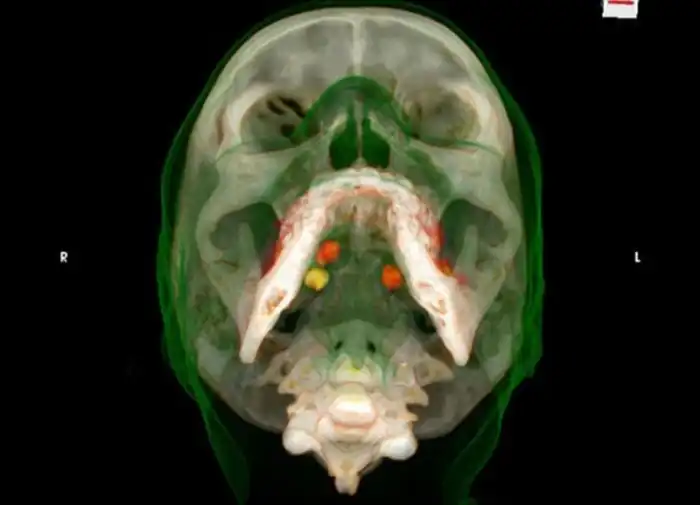

Пакетики с кокаином под языком

Попытка провезти кокаин под языком

Одна часть кокаина под языком, а вторая в желудке